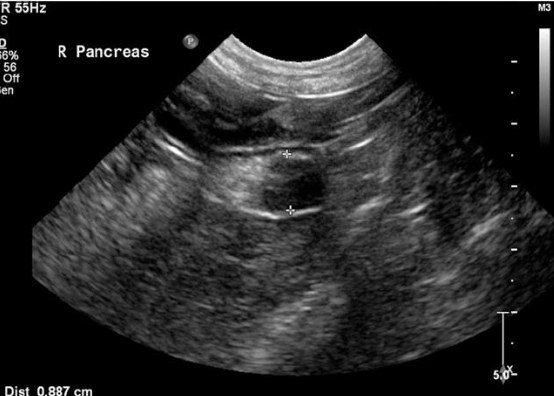

is imaging helpful for diagnosing insulinomas?

-can be useful for surgical preparation

-thoracic and abdominal rads often unremarkable

-abdominal U/S can identify a mass 50% of time (better at ID'ing mets)

-abdominal CT more sensitive for ID'ing primary lesions, not specific for metastatic disease